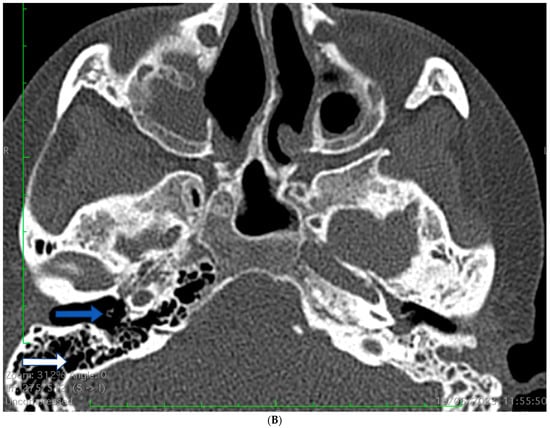

2.1. Case 1